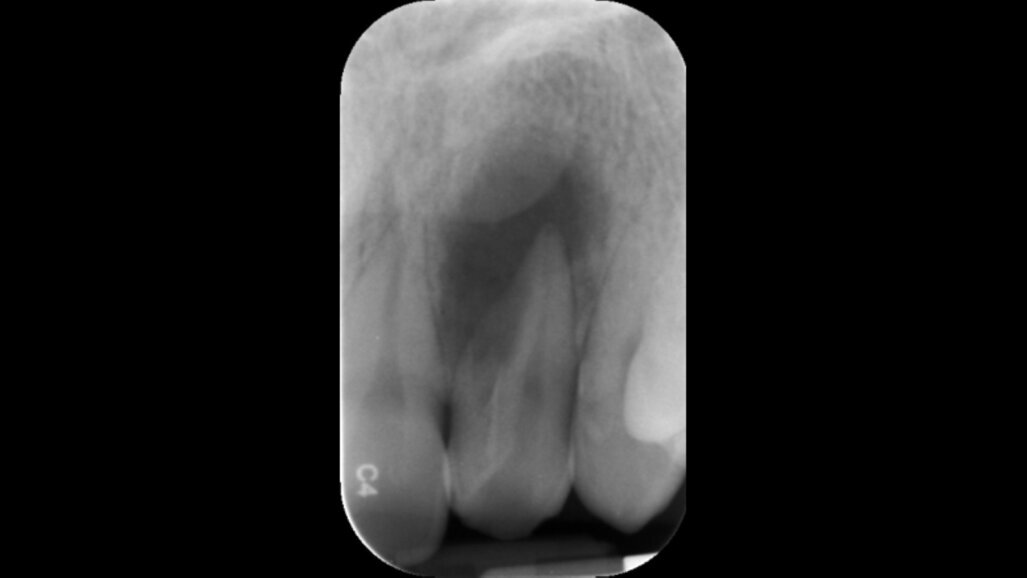

Segundo a OMD, o objetivo principal desta formação passa por “Perceber o potencial papel da infeção cruzada no sucesso do tratamento endodôntico; discutir técnicas e materiais de desinfeção do campo operatório e sistema de canais radiculares; debater certos aspetos da persistência microbiana e o seu envolvimento no fracasso endodôntico”.

No final deste Curso clínico, o formando deve adquirir competências no âmbito de “compreender de que forma a infeção cruzada pode ser minimizada”, assim como, “rever técnicas contemporâneas de desinfeção do sistema de canais radiculares”.